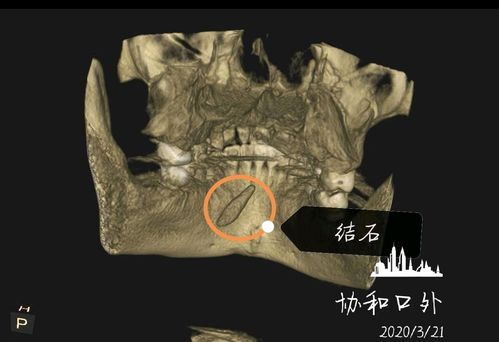

颌下腺导管结石

颌下腺导管结石,颌下腺结石自己出来了

[科普]颌下腺导管结石

左颌下腺导管结石导管结石ct影像治疗1,保守治疗很小的唾液腺结石或者

刘某,男,36岁,右侧颌下腺导管结石,ct片可见右侧口底前份,以及靠近

颌下腺导管结石ct图片